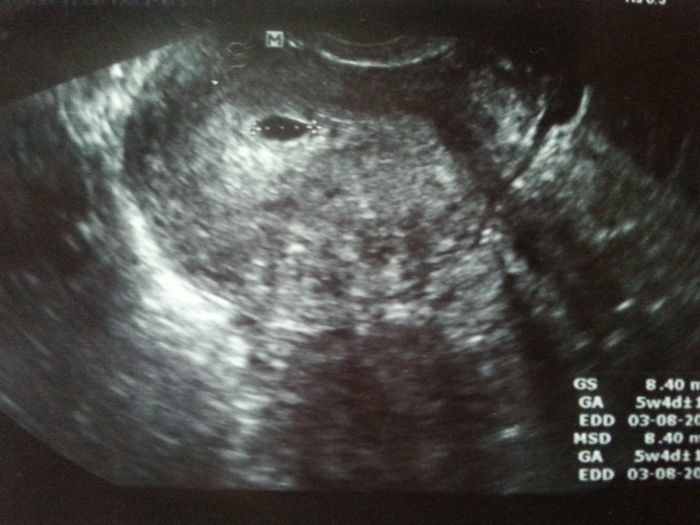

Ahojte holky. Nejak mi to neda ale musim se vas zeptat. Co vidite na UTZ? Nekdo mi totiz rika ze vidi jeste jeden ten vacek na prave strane, nekdo zase ze je to mimodelozni na te prave strane. Co si myslite vy? To na levo je kde ma tudiz v deloze :-D ale to na pravo? Lekar si toho nevsiml -_-

[675044]Very na pravo už nevidim nic... :O

[675118] toto kazdy mysli. Ja sama jsem z dvojcat tak me budti desi a nebo mam smulu :D

To už je moc daleko ne? Nemůže to být jen stín?? Pochybuju, že by to dr. přehlídnul...